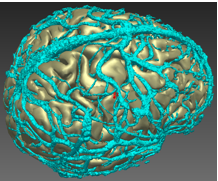

3D-multimodal imaging and computer-assisted navigation

Hamartomas in the hypothalamus can give rise to severe epilepsy that is not controlled with medication and is not accessible to surgery.

A treatment option is to destroy the abnormal area with laser light from a probe inserted into the brain. The challenge is to find a safe trajectory that does not damage critical structures or blood vessels in the brain. We have developed 3D-multimodal imaging to display these structures and computer-assisted navigation to find safe trajectories.